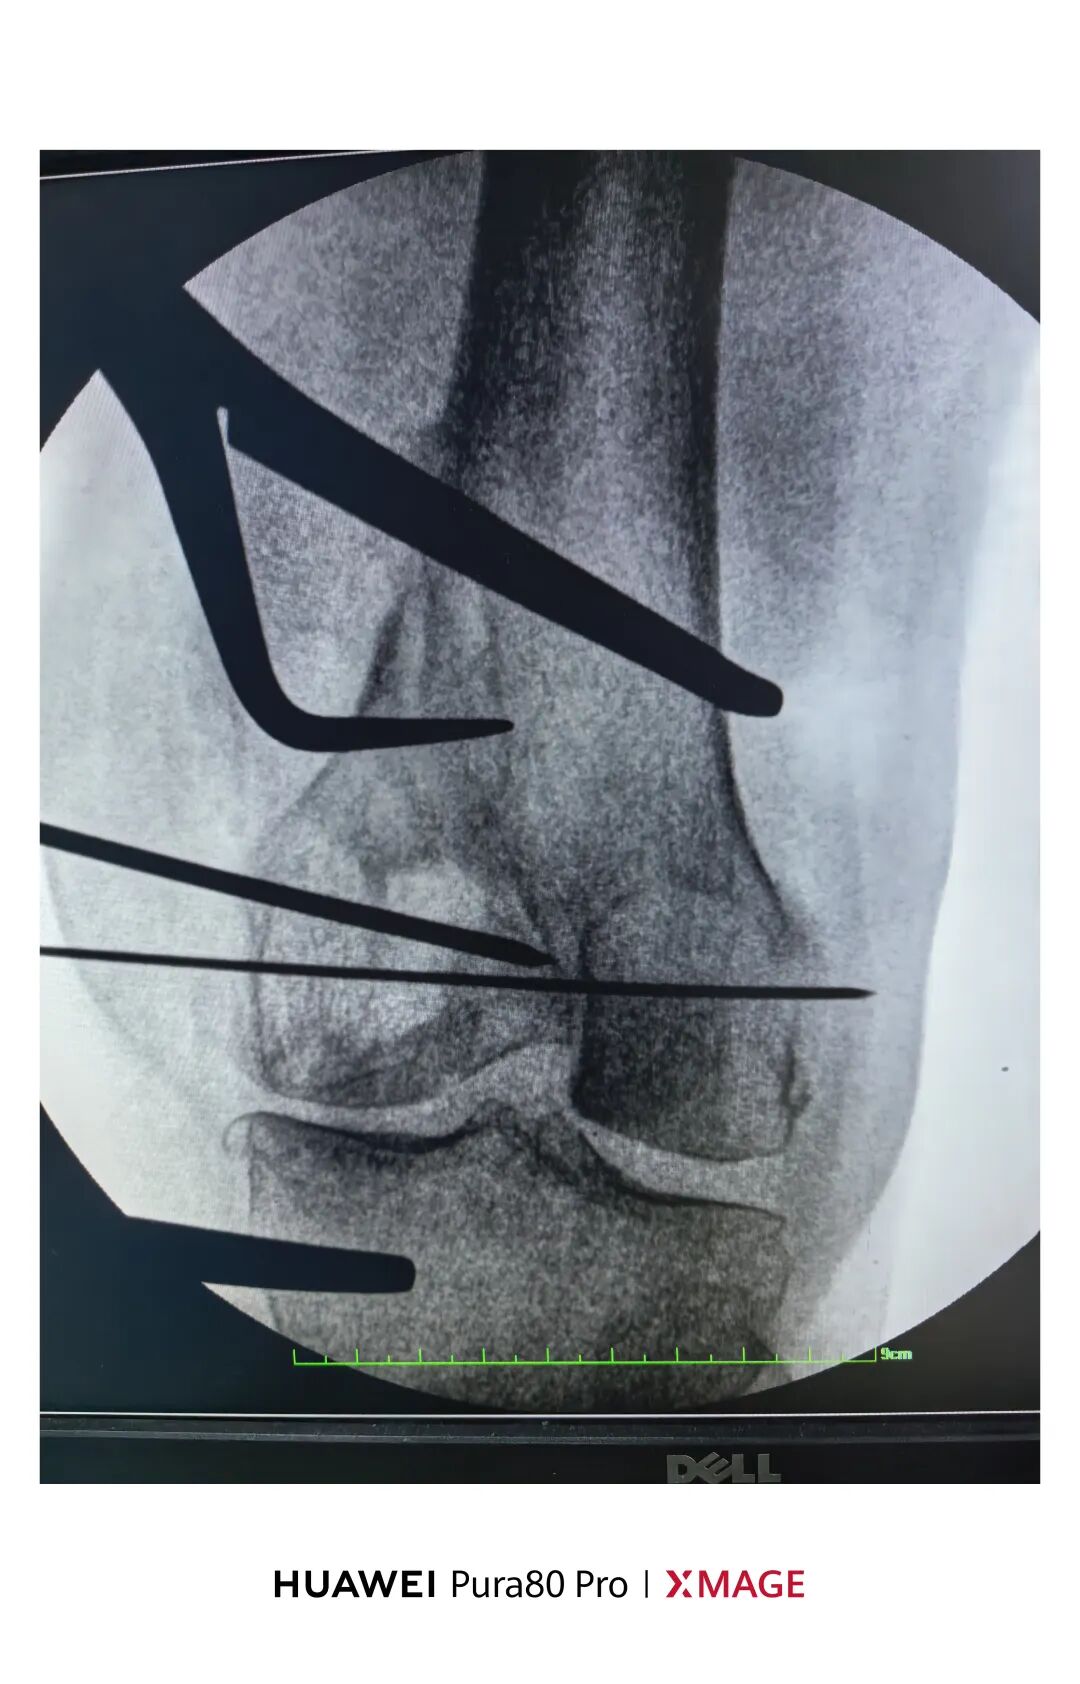

5个月前在魔都骨折,当时建议手术

患者拒绝并签字

给予支具固定

现畸形、疼痛伴活动受限来院

复位满意,力线纠正